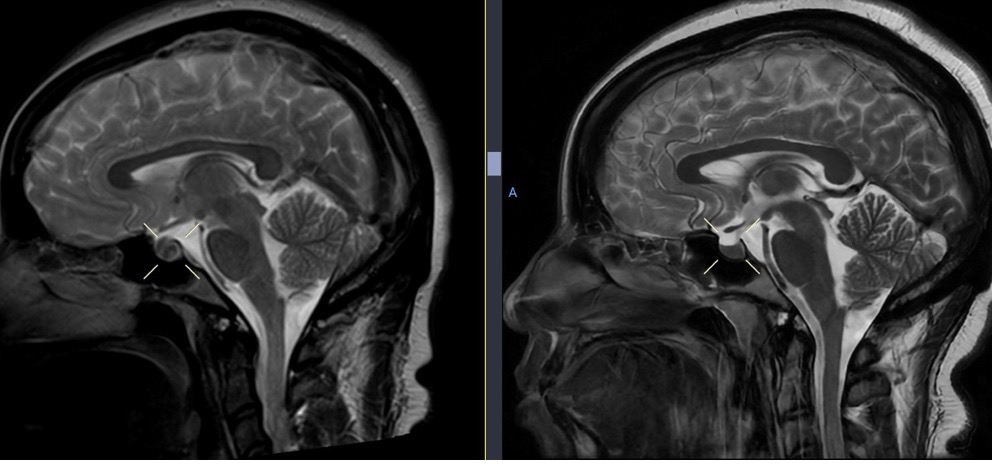

Outcome and follow-up. The plan was to continue anticoagulation and reassess clinically and with neuroimaging in 6 months. At her 6-month visit, she had no headache, a normal brain MRI, and no longer needed anticoagulation (Figures 9-11).

Fig. 9. Initial brain MRI (left) shows distention of the cerebral venous sinuses, with subsequent resolution 6 months later on follow-up MRI (right).

Fig. 10. Diffuse pachymeningeal thickening and enhancement on initial brain MRI (left), with interval resolution on follow-up MRI 6 months later (right).

Fig. 11. Initial brain MRI (left) shows enlargement of the pituitary gland, with resolution on follow-up MRI 6 months later (right).

This patient initially presented with headache, photophobia, neck pain, left upper extremity paresthesia, and later with blurred vision and loss of balance. These symptoms are suggestive of intracranial hypotension secondary to CSF volume loss4,6. Although not initially recognized, the brain MRI with and without contrast demonstrated classic signs of intracranial hypotension, including pachymeningeal enhancement, engorgement of dural venous sinuses, and pituitary enlargement4. These signs are subtle findings that may be easily overlooked if not searched for specifically. However, another classic feature of intracranial hypotension, bilateral subdural hematomas, developed later7. Brain sagging, which may be seen with intracranial hypotension, was not observed.